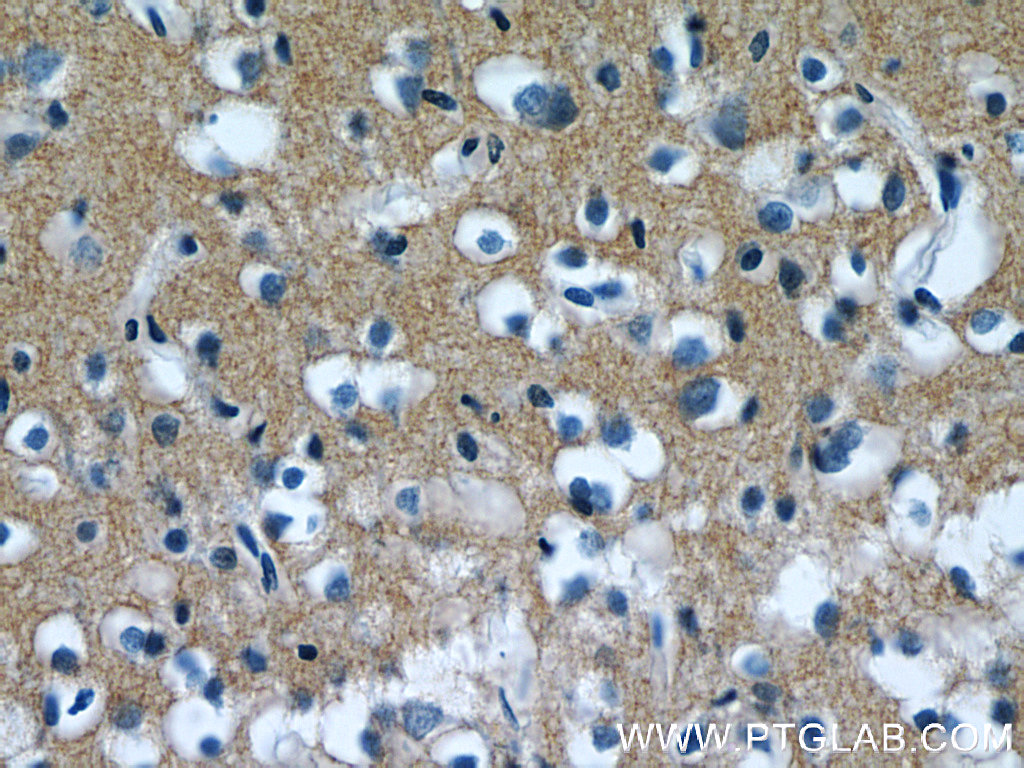

human brain tissue were subjected to SDS PAGE followed by western blot with 12591-1-AP(AKAP7 antibody) at dilution of 1:500 human brain tissue were subjected to SDS PAGE followed by western blot with 12591-1-AP(AKAP7 antibody) at dilution of 1:500 Immunofluorescent analysis of HepG2 cells, using AKAP7 antibody 12591-1-AP at 1:25 dilution and Rhodamine-labeled goat anti-rabbit IgG (red). Immunofluorescent analysis of HepG2 cells, using AKAP7 antibody 12591-1-AP at 1:25 dilution and Rhodamine-labeled goat anti-rabbit IgG (red). IP Result of anti-AKAP7 (IP:12591-1-AP, 4ug; Detection:12591-1-AP 1:300) with mouse brain tissue lysate 4000ug. IP Result of anti-AKAP7 (IP:12591-1-AP, 4ug; Detection:12591-1-AP 1:300) with mouse brain tissue lysate 4000ug. Immunohistochemistry of paraffin-embedded human brain tissue slide using 12591-1-AP( AKAP7 Antibody) at dilution of 1:50 (under 10x lens) Immunohistochemistry of paraffin-embedded human brain tissue slide using 12591-1-AP( AKAP7 Antibody) at dilution of 1:50 (under 10x lens) Immunohistochemistry of paraffin-embedded human brain tissue slide using 12591-1-AP( AKAP7 Antibody) at dilution of 1:50 (under 40x lens) Immunohistochemistry of paraffin-embedded human brain tissue slide using 12591-1-AP( AKAP7 Antibody) at dilution of 1:50 (under 40x lens)

Human brain tissue, human heart tissue |

IHC : 1:20-1:200